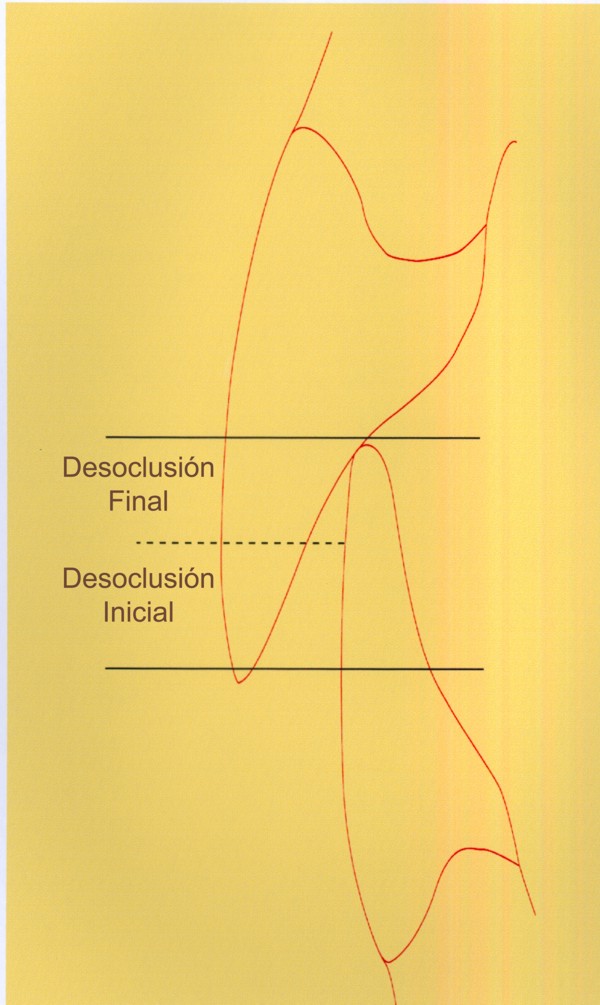

RESUMEN Más allá en el tiempo, respecto de las razones más frecuentes de fracasos como temperatura de fresado, infecciones, falta de fijación inicial, falta de higiene, etc., la OCLUSIÓN recibe sobre sí, la responsabilidad de la permanencia de la osteointegración, como así de la ortofunción del sistema todo. Sometimes ago,conserning the most frecuent reason of failures such as the strawberry action temperature, infections and lack of hygiene…etc.,the OCLUSION has itself the responsability af having the osteointegration well as the allsistem ortofunction . DESARROLLO La valoración de los fracasos en IMPLANTOLOGÍA es difícil de contabilizar sobre todo después del año, ya que el confort logrado por lo general, hace que el paciente realice correctamente sus primeros controles, y después; apoyado en su bienestar; intente subconscientemente olvidar ese período de su vida, que si bien le devolvió su capacidad masticatoria, fonética, social, etc., le ocasionara gastos, molestias, sufrimientos. … la APLICACIÓN de dichas fuerzas, requiere de una exactitud mucho mayor. Los esquemas propuestos a través de los años, no son muchos ni muy variados… I-Evitar las fuerzas tangenciales. II-Repartir las fuerzas lo máximo posible. Sin embargo, muchas veces se confunden los conceptos anteriores con criterios inexactos. Por ej: a-Reducción de las caras vestibulares y palatinas, aceptando que la menor superficie de intercontactos reduce la carga. b-Utilización de la Función de Grupo Posterior, en la creencia de que repartiendo el esfuerzo en las piezas posteriores, ganamos resistencia; a la potencia ejercida por los músculos. c-No permitiendo el contacto excéntrico de un canino implantado, para aliviarlo de las cargas laterales, sobre cargando de esta manera la tabla premolar-molar en el Lado de Trabajo. Algunos conceptos aislados, que forman parte de toda una filosofía de la Oclusión (OCLUSIÓN ORGÁNICA), sean tal vez de ayuda para echar luz sobre los preceptos anteriores. 1º-PROPORCIONES FUNCIONALES DE UN PAR OCLUSAL En la figura siguiente, observamos la relación final masticatoria de un PAR OCLUSAL: En el se ven los contactos puntiformes, producto del choque de superficies redondeadas contra superficies redondeadas («Solo pueden encontrarse en un punto» Ref: Principios Mecánicos Esferoidales.W.Mc.Horris.) Si Miramos con atención este tipo de contactos interoclusales, veremos que la superficie actuante es mucho menor que la superficie total de la cara oclusal: 45% (Fig.1) Por lo tanto, si no es por razones del Pilar de Emergencia para no crear un espacio biológico inadecuado… ¿POR QUÉ REDUCIR LA CARA OCLUSAL VESTÍBULO LINGUALMENTE? (Figs. 2-3-4-5) Si observamos con atención las figuras 2-3-4-5, veremos desde todos los planos , que el área contactante es muy reducida respecto del ancho oclusal total, siendo las fuerzas resultantes , AXIALES al eje implantario. 2º-FUNCIÓN DE GRUPO POSTERIOR. FUNCIÓN CANINA. Tres son las razones por las cuales nos inclinamos a la utilización de la Función Canina. En cambio, en el esquema de FUNCIÓN CANINA, podemos observar que el BRAZO DE POTENCIA, es prácticamente igual al de RESISTENCIA, equilibrando de esta manera la palanca y destruyendo mucho menos las estructuras de soporte(Interface I-H) (Fig. 7) Otra de las razones de peso en este tema es la DIFERENCIA DE ANGULACIÓN que existe entre la cara palatina del canino y las vertientes contactantes del sector premolar-molar. A MAYOR ANGULACIÓN, MENORES FUERZAS LATERALES(Perpendiculares al Plano), y por lo tanto , menor destrucción de la interface Hueso-Implante(Figs. 9-11). DIFERENCIAS EXCITATORIAS DE LOS GRUPOS MUSCULARES. Por último debemos considerar que el intercontacto dentario del sector anterior, estimula excitatoriamente a las fibras anteriores y verticales del temporal (Figs.12-13-14-15), mientras que los contactos posteriores lo hacen con la cincha pterigo-maseterina(Fig. 16-17-18-19) Por lo tanto ,si se comprende el fisiologismo de estos conceptos, es sencillo entender que la sobrecarga de los sectores posteriores es nocivo generando fuerzas tangenciales de Alto Potencial Patológico. 3º-FUNCIÓN DE GRUPO ANTERIOR Las ventajas de un Brazo de Resistencia mayor se acentúan cuando tenemos el esquema de FUNCIÓN DE GRUPO ANTERIOR. Además, debemos tener en cuenta que, durante la función de un Ciclo Masticatorio, es más importante la Desoclusión Final que la Desoclusión Inicial, ya que al ser más larga esta última, es durante el transcurso de su deslizamiento cuando se ejercen fuerzas laterales mayores(Fig. 21) A medida que la punta del canino inferior se acerca a la O.R.C., o sea al Punto de Contacto Intercanino, las fuerzas laterales disminuyen en virtud del acortamiento del brazo de potencia de la palanca, hasta que, al terminar su recorrido, la fuerza es proyectada axialmente sobre el eje del canino superior, debido a que, al margen de la intensidad que la fuerza trae durante el cierre, la dirección de la misma «apunta» en esa dirección. Por eso decimos que los caninos Axializan el Ciclo Masticatorio. Si estamos imitando en lo posible a la naturaleza, no olvidemos este detalle que los dientes naturales provéen, para evitar las fuerzas laterales del canino a la hora de realizar la supraestructura coronaria del mismo. Es ahora menester acentuar que la problemática concreta se manifiesta, no durante la función, sino durante la PARAFUNCIÓN… Cuando estudiamos recorridos de la Dinámica Mandibular, desde el conocido Bicuspoide de Posselt hasta cualquiera de los registros pantográficos, estamos invirtiendo la dirección del movimiento… A.- El primer premolar es el más anterior de la tabla oclusal posterior. Por lo tanto el brazo de resistencia es el mayor de dicha tabla. B.- El lateral, como parte del grupo anterior, cuenta con un empotramiento tipo «clavo largo», y el interseptum lateral -canino, que se opone a la fuerza, es mucho más grueso que la tabla vestibular del primer premolar(Fig.23) C.- Condiciones, las dos anteriores que se favorecen considerablemente, si al enfundar el lateral se logra junto al central una Función de Grupo Anterior. D.- De manera más artificiosa, la instalación de una placa de relajación, soluciona durante la noche lo nocivo de las fuerzas laterales. Veamos un par de casos, como ejemplo de lo dicho: Paciente de 54 años que se presenta a la consulta portando prótesis completa superior y antagonista natural que soporta fundas de porcelana. Obsérvese la función de grupo posterior ejercida, y las consecuencias de la misma: Otro paciente que presenta fractura de la cúspide fundamental de un onlay de porcelana antagonista de cinco piezas implantadas (Fig.27). Radiográficamente se observa la desinserción de uno de sus abuttments cementados (Fig.28). En el Lado de Trabajo (LT), no existe el canino encargado de desocluir la zona afectada (Figs.29-30) Como corolario, cabe entonces una pregunta: ¿Es el Implante en el canino quien debe preservar de patología oclusal al resto del sistema…. ¿Es el Implante…un medio…o un fín? BIBLIOGRAFÍA 1- Dibujos tomados del libro del mismo autor: «OCLUSIÓN ORGÁNICA… UN CAMINO HACIA LA REHABILITACIÓN ORAL»(en preparación) 2- «NEUROFISIOLOGÍA DE LA OCLUSIÓN» 3- «OCLUSIÓN Y FUNCIÓN» 4- «FUNDAMENTOS, TÉCNICAS Y CLÍNICA EN REHABILITACIÓN BUCAL» 5- «OCLUSIÓN Y REHABILITACIÓN» 6- «DISFUNCIÓN TEMPOROMANDIBULAR» 7- «PROCEDIMIENTOS CLÍNICOS Y DE LABORATORIO DE OCLUSIÓN ORGÁNICA» 8- «ESTUDIO ELECTRÓNICO DEL MOVIMIENTO MANDIBULAR» 9- «OCLUSIÓN: CONCEPTO PARA EL CLÍNICO» 10- «IMPLANTOLOGÍA CONTEMPORÁNEA» 11- «OCLUSIÓN Y DIAGNÓSTICO EN REHABILITACIÓN ORAL» 12- «PRINCIPIOS DE OCLUSIÓN»

Según este esquema, un canino implanto-soportado que asumiera su responsabilidad como integrante de una Oclusión Mutuamente Protegida, sólo se vería afectado por las fuerzas laterales en el inicio de la Desoclusión final, disminuyendo la misma a medida que se acerca al punto de contacto intercanino.

Si por el contrario la Función Canina está presente, lógicamente el canino recibirá las fuerzas laterales, ya que el inferior estará más tiempo en contacto con la Desoclusión Final que con la Inicial.